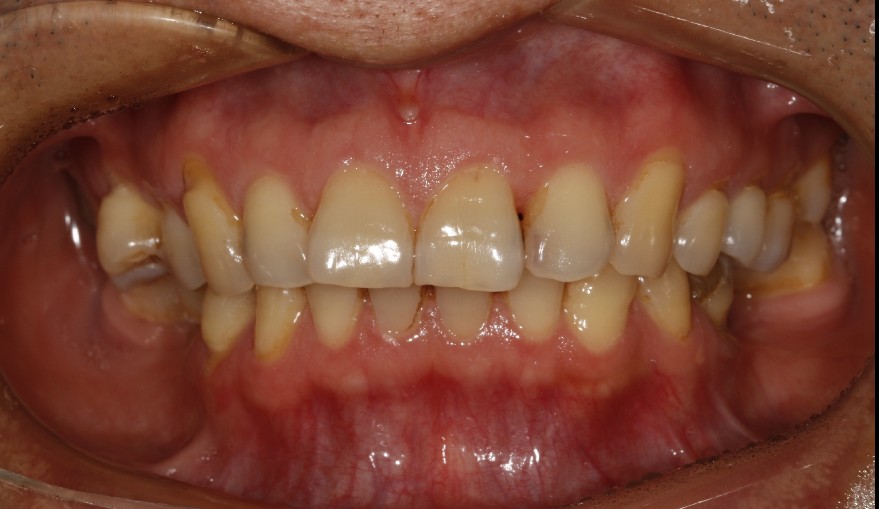

患者男,四十四岁,36,46缺失已植入种植体,附着龈不足,缺牙区牙槽嵴呈刀刃状,缺牙区咬合间隙及近远中间隙尚可。可行游离牙龈移植术增宽种植体周围附着龈的面积。